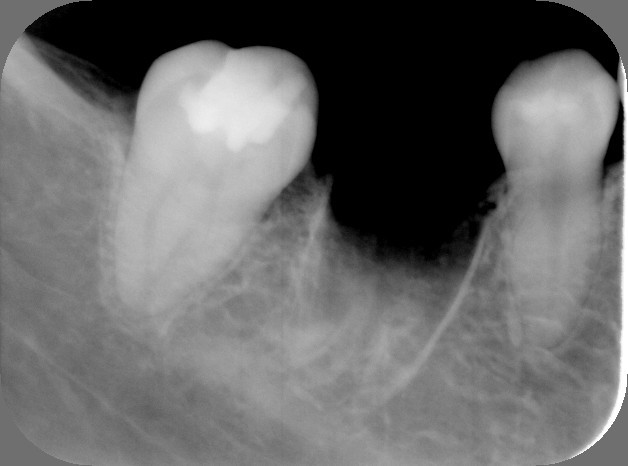

1.左から2番目が大きな虫歯で抜歯が必要です。